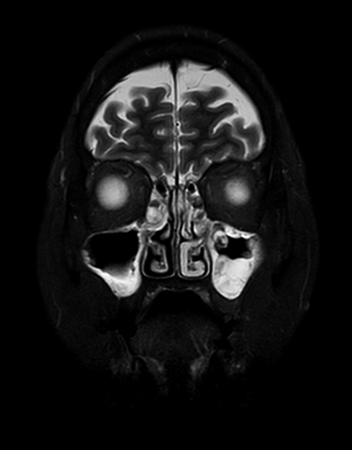

Coronal T2w STIR